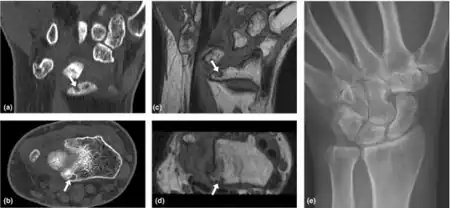

Loss of Motion-Wrist of rheumatoid arthritis individual a-e)

• Loss of motion (symptom): the patient notices that the joint (or many joints) do not move as far as they used to or need to. Loss of motion is a feature of more advanced stages of arthritis including osteoarthritis, rheumatoid arthritis and ankylosing spondylitis.